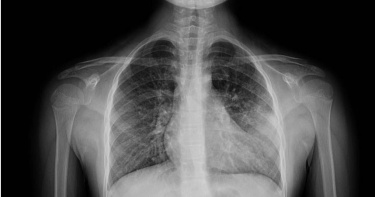

家長要小心!兒科醫師廖穗綾分享一個驚險案例,一名1歲多的幼童被阿嬤餵食整顆花生,幾天後出現咳嗽、喘鳴聲等症狀,送醫檢查驚見「肺部已經開始塌陷」。為了取出這顆卡死在氣管的異物,醫療團隊耗時近2小時,在狹小氣道裡反覆嘗試才成功夾出。看著住進加護病房的孩子,醫師忍不住怒喊:「到底為什麼要餵小小孩吃整顆花生?」基隆長庚醫院兒科教授級主治醫師廖穗綾今(12)日在粉專發文指出,上週遇到一名緊急送來的1歲多幼童,據了解,孩子在3、4天前被阿嬤餵食了花生,隨後開始出現咳嗽與喘鳴聲,雖然剛開始症狀不明顯,但隔天追蹤X光發現,「肺部已經開始塌陷」,這絕非小事。當晚該童轉入加護病房,廖醫師的丈夫賴醫師緊急召集加護病房團隊與資深技術員,準備透過支氣管鏡取出異物。然而,手術過程極度艱難,廖穗綾透露那顆花生已經卡了三天、肉芽長出來,「整顆又大又肥,死死塞住支氣管」;賴醫師更直言,他從來沒有遇過這麼困難的案例。廖穗綾續指,醫師在孩子狹小的氣道裡反覆嘗試將近2個小時,就在幾乎快要放棄時,那顆「會跳舞的花生」終於彈動了一下,醫療團隊隨即成功網住、夾出,那一刻大家才鬆了一口氣。雖然孩子成功救回,但廖穗綾忍不住怒轟這已不是第一個案例,甚至今日又看到兒科急診醫師吳昌騰分享其他孩子因被餵食花生而進開刀房。針對許多家長常說「只吃一顆而已」、「我有在旁邊看著」、「我們以前都這樣長大」,廖穗綾指出,醫療現場看到的卻是「氣道發炎腫脹」、「肉芽生成」、「肺部塌陷」,最後只能住進加護病房插氣管鏡。「我們到底還要講幾次?到底為什麼要給小小孩吃整顆花生?」廖穗綾強調,小小孩的吞嚥與咀嚼能力尚未成熟,兩者間協調不夠穩定,若吞嚥瞬間聲帶剛好打開,比較硬且不易咬碎的食物就可能滑入氣管中。廖穗綾提醒家長,花生、堅果類、湯圓、硬芭樂、椰果,以及任何「硬、滑、不易咬碎」的食物,請至少等到孩子3至4歲以上再嘗試。